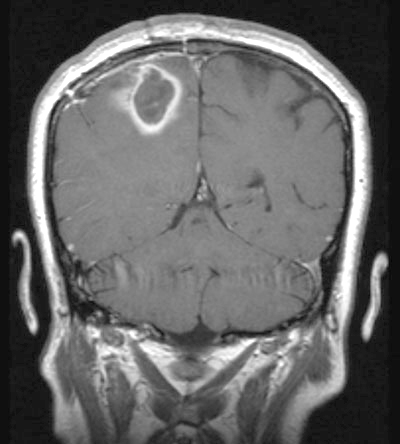

A 48-year-old woman presented to the emergency department (ED) with headache and left-sided weakness, initially diagnosed from a computed tomography (CT) scan as a right parietal stroke. Magnetic resonance imaging (MRI) showed a parietal mass consistent with a tumour (Box 1, A). Using stereotactic craniotomy, purulent material was drained from the lesion, and S. milleri and Actinobacillus actinomycetemcomitans were grown on culture.

After 8 weeks’ treatment with intravenous benzylpenicillin, ceftriaxone and metronidazole, the woman’s neurological deficits resolved and an MRI scan showed scar tissue in the right parietal lobe without reaccumulation of pus.